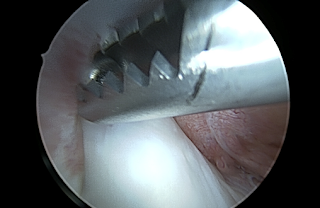

Notchplastiek

Jacco begon met de notchplastiek. Hij haalde met de shaver eerst wat bindweefsel weg, om vervolgens bij het bot uit te komen. Het bot zag er van binnen wat gelig uit. Met de boor freesde hij zoveel mogelijk bot weg, om de kruisband ruimte te geven om te bewegen. Hoe verder hij kwam, hoe voorzichtiger hij te werk ging om de kruisband niet te beschadigen. Daarna ruimde hij her en der nog wat weefsel op. Jacco deed vervolgens, met de camera nog in mijn knie, de Lachman-test, die een mooie stabiele knie liet zien. Hij bewoog mijn knie naar strekking en ik zag met eigen ogen dat ik er weer helemaal kwam. De kruisband klemde niet meer, had ruimte.

Actiefoto – ruimte maken

Notchplastiek geslaagd: de kruisband ligt mooi vrij.